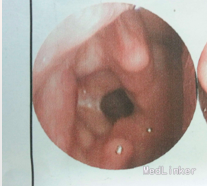

喉镜检查示:双侧声带前中分粘连,声带活动可,闭合差。